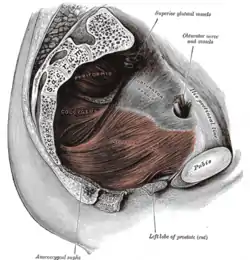

| Pelvic floor | |

Pathophysiology

It is the loss of small amounts of urine associated with coughing, laughing, sneezing, exercising or other movements that increase intra-abdominal pressure and thus increasing the pressure on the bladder. The urethra is normally supported by fascia and muscles of the pelvic floor. If this support is insufficient due to any reason, the urethra would not close properly at times of increased abdominal pressure, allowing urine to pass involuntarily.